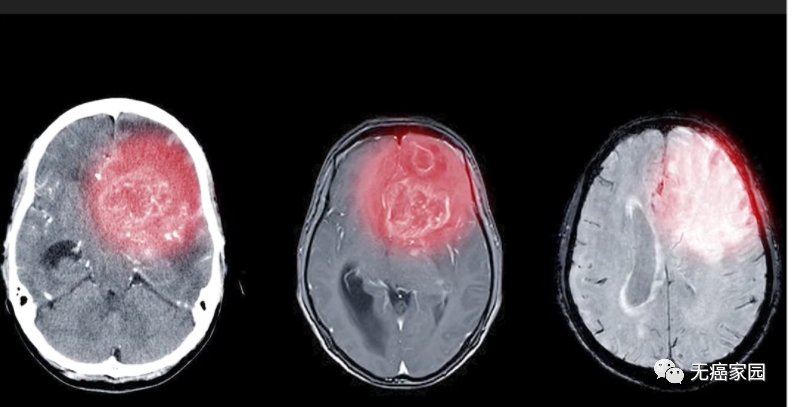

患者5的脑部MRI扫描图

A:在树突状细胞注射之前

B:完成肽脉冲树突状细胞疫苗系列的2个月后

(箭头所指区域在树突状细胞疫苗治疗后消失)